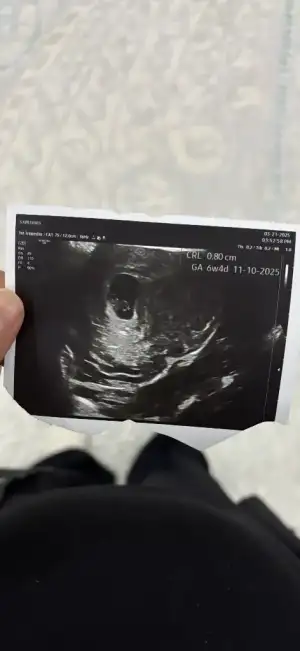

Yazmayı unuttum 6 haftalık karından bakıldıMerhaba benim bebeğime de bakabilir misiniz

Kız bebek gibiBenimde 8+2 haftalık bakar mısınız acaba cinsiyeti ne ?

Yaa üzüldüm erkek istiyordum hayırlısıyla,başka bir konuda benimkiyle resmen aynı ultrasyon resmi olan birine erkek demişlerdi ama yanılma payı var mı acabaKız bebek gibi